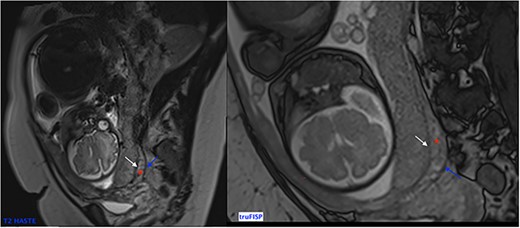

Her MRI showed some thick linear and round bands arising from the maternal side of the placenta seen in low signal in single-shot fast spin echo (SSFSE) T2-Weighted images (HASTE) and in high signal on Balanced Steady State Free Precession (bSSFP) (True Fisp), corresponding to dark intra-placental bands (Fig. 2). The most important finding was myometrial thinning and the bulging of the placenta within the Cesarean scar as well discontinuity in the urinary bladder wall with its invasion by the placental tissue (Fig. 2). These abnormalities were associated to some tortuous bands in a signal on all sequences corresponding to vessels. The diagnosis of placenta percreta was then made and the patient was referred to the obstetrics department for urgent care.

(a)–(d) Sagittal sequences showing dark intra-placental bands (arrows) in low signal in HASTE sequences and in high signal on truFISP. (e) Sagittal HASTE and (f) coronal truFISP sequences showing myometrial thickening and discontinuity in the bladder wall as well as its invasion by the placental tissue (arrow).